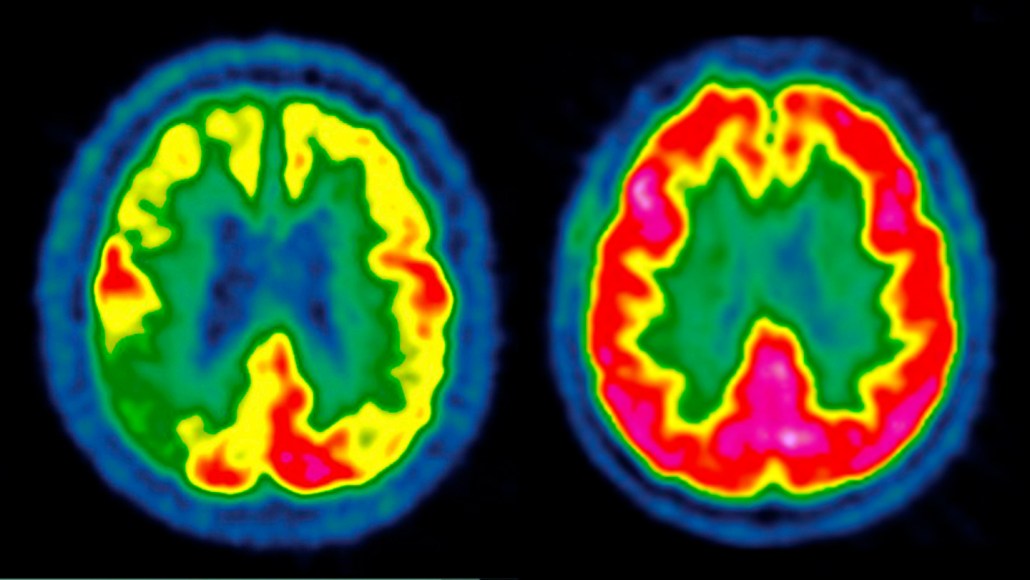

Two brain scans shown side by side with highlights in primary colors, against a black background. The left scan has more blue and green, while the right scan has more higlighted in red.

Scientists have previously shown that the brain of a person with Alzheimer's disease (left) can have diminished activity represented from low (blue) to high (red) compared with a healthy person (right). In two new clinical trials, scientists had hoped to delay disease progression by giving patients a GLP-1 drug, but the treatment failed.

CENTRE JEAN-PERRIN/Science Source